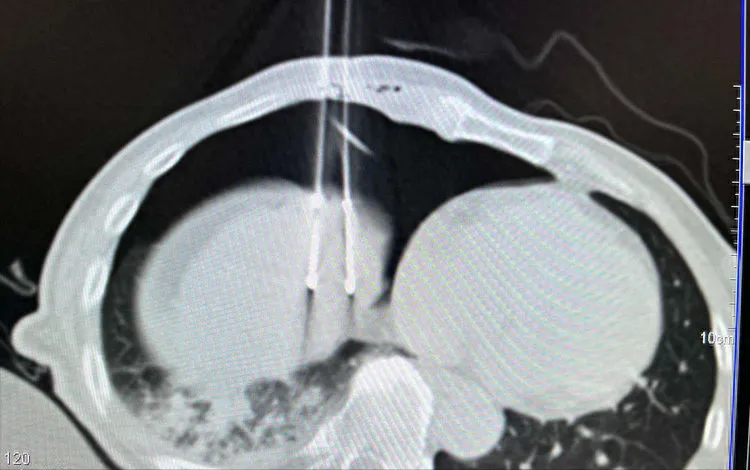

传统采用一根或两根穿刺针的方法直接建立人工气胸,容易造成肺损伤,而且术后排气也面临着一定困难。日本国立癌症中心小泽教授团队曾应用了一种创新性人工气胸技术——肝导向入路seldinger技术。

该技术在肝膈顶肿瘤、纵膈肿瘤及肾和肾上腺肿瘤的穿刺消融和活检手术中,技术成功率100%,副作用小,特别是避免了肺损伤。我曾采用此技术,建立人工气胸和人工胸水大约做了数十例手术,全部成功,效果不错。

注入500ml气体(最好是CO2),建立人工气胸将肺与膈肌分离开;

冷冻消融清晰显示足够的消融范围;

通过导管抽出气体,肺复张,人工气胸消除;

▲利用肝导向入路seldinger技术,在人工气胸下行膈顶肝癌冷冻消融术。